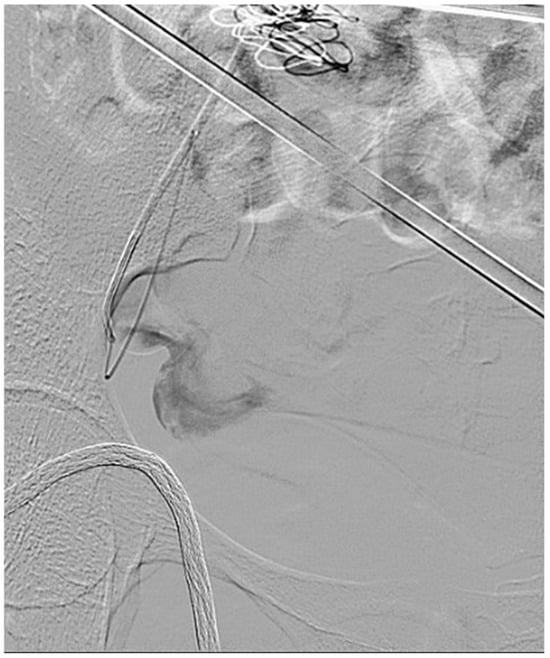

2.2. Procedure and Technique